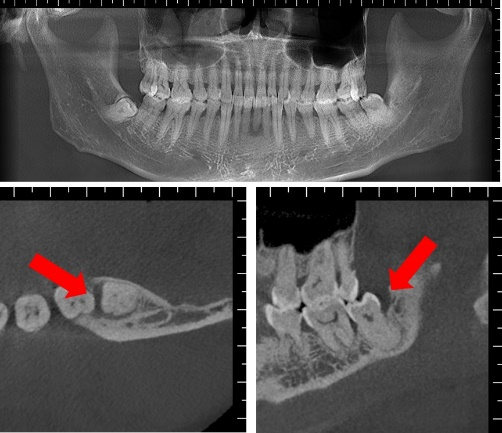

通过口腔专科检查及CBCT检查,发现患者的左下智齿近中阻生,其远中及近中可探及牙周深袋,左下第一磨牙黏膜转折处可见窦道,左上智齿阻生。根据病史及发病部位考虑,这名患者最终被诊断为智齿反复发炎导致的“牙源性皮瘘”。